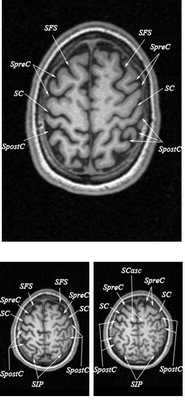

Знание анатомии мозга очень важно для правильной локализации патологических процессов. Ещё более важно оно для изучения самого мозга с помощью современных «функциональных» методов, таких как функциональная магнитно-резонансная томография (fMRI), и позитронно-эмиссионная томография. С анатомией мозга мы знакомимся ещё со студенческой скамьи и существует множество анатомических атласов, в том числе и поперечных сечений. Казалось бы, зачем ещё один? На самом деле, сравнение МРТ срезов с анатомическими приводит к множеству ошибок. Это связано как со специфическими особенностями получения МРТ изображений, так и с тем, что строение мозга очень индивидуально.

Представленная страница сайта основана на специальном изучении МРТ головного мозга здоровых лиц. Для этого изображения получали с минимальной величиной воксела (1 мм в каждом измерении), что исключало наслоения борозд. Каждая из структур прослеживалась в трёх реконструированных плоскостях путём её выделения с помощью компьютерной программы. Мы рассматривали различные анатомические варианты, что обсуждается в работе. В результате, учитывая вариабельность строения мозга, подобран условно «стандартный» мозг. Поскольку на сайте нереально представить 128 срезов в каждой из основных плоскостей, мы ограничились только каждым пятым срезом. Основные срезы в поперечной плоскости даны без наклона назад (угол 0º). Под ними для представления о изменении соотношения анатомических структур демонстрируются срезы, выполненные на тех же уровнях, но с наклонами назад -15º и -30º.

Список сокращений

Борозды

Междолевые и срединные

SC - центральная борозда

FS - Сильвиева щель (латеральная борозда)

SpreC - предцентральная борозда

SFS - верхняя лобная борозда

SpostC - постцентральная борозда

SIP - внутритеменная борозда